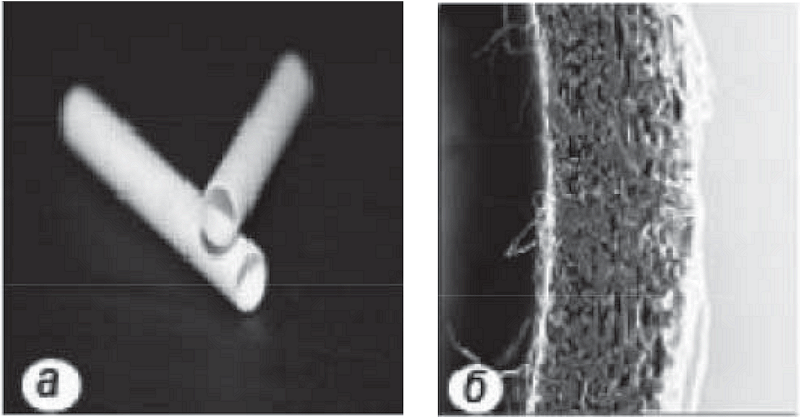

Протезы кровеносных сосудов из БМ в виде трубчатых образцов диаметром 1,1±0,2 мм и толщиной стенки 320±10 мкм (рис. 1) получали путем электроформования на установке «NANON-01A» фирмы «MECCCo.»(Япония) в Институте высокомолекулярных соединений Российской академии наук в соответствии с оригинальной методикой [3] (рис. 1).

Рис. 1. Внешний вид протеза (а) и его стенки (б) из поли(L-лактида) для протезирования аорты крысы